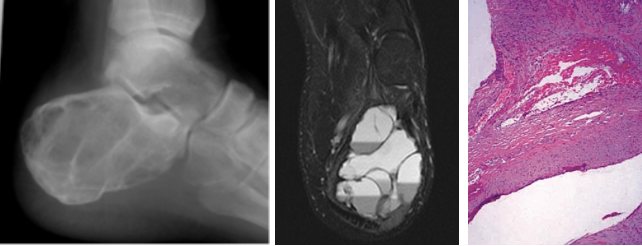

What is seen on imaging of aneurysmal bone cyst

What is the histology of aneurysmal bone cyst?